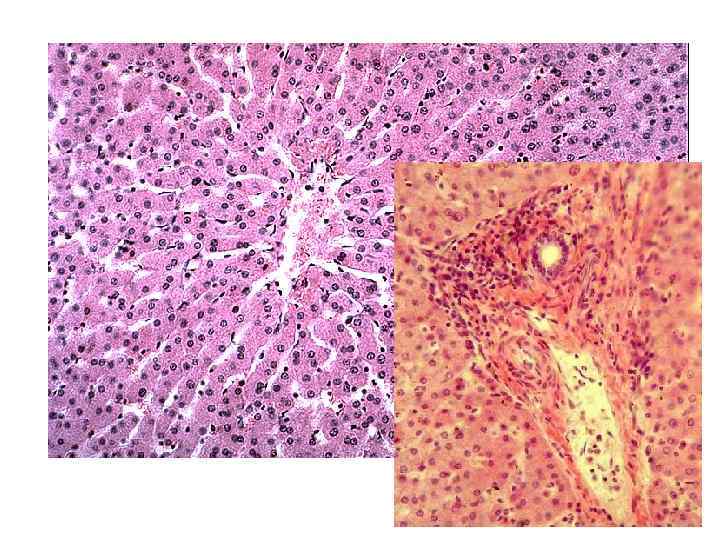

ПЕЧЕНЬ – ПАРЕНХИМАТОЗНЫЙ ДОЛЬЧАТЫЙ ОРГАН

ПЕЧЕНОЧНЫЕ БАЛКИ ЦЕНТРАЛЬНАЯ ВЕНА ЖЕЛЧНЫЙ КАПИЛЛЯР ПОГРАНИЧНАЯ ПЛАСТИНКА СИНУСОИДНЫЙ КАПИЛЛЯР МЕЖДОЛЬКОВАЯ ВЕНА КЛЕТКА КУПФЕРА ЭНДОТЕЛИОЦИТ ПОГРАНИЧНАЯ ПЛАСТИНКА

Региональные особенности гепатоцитов Гепатоциты периферии – депонирование жиров, детоксикация и биосинтез желчи; Гепатоциты центра – депонирование гликогена.

Печеночный ацинус Печеночная долька При острой гипоксии – страдают промежуточная и периферические зоны. При повреждении токсическими веществами – центральная. Центральная вена триада

ПЕЧЕНОЧНАЯ ДОЛЬКА, ПОРТАЛЬНАЯ СВ СВ МВ АЦИНУС А